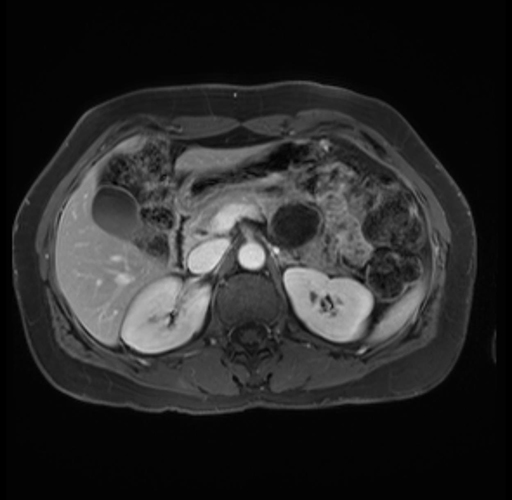

Imaging Analysis

Look through the patient's CT scan to identify any areas of concern for the necessary procedure.

Based on your CT findings, which issue(s) are present and would give reason for "planned slowing down moment(s)" in this case?